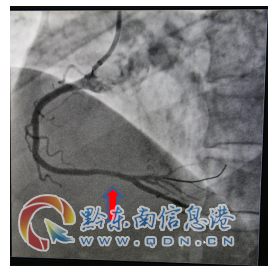

該患者入院查肌鈣蛋白、心肌酶增高,復(fù)查心電圖提示“Q波加深、ST段下移較前明顯”,結(jié)合輔助檢查結(jié)果陳文海主任對(duì)患者病情診斷為急性心肌梗死,考慮患者合并有糖尿病、甲亢等多種病癥,病情緊急,需按照胸痛中心急性心肌梗死流程緊急處理。經(jīng)過(guò)該院心血管內(nèi)科專(zhuān)家的會(huì)診評(píng)估,認(rèn)為及早行冠脈介入診療對(duì)患者是有益的。征得該患者及家屬的同意后,立即啟動(dòng)導(dǎo)管室行冠脈造影檢查,造影提示右冠脈遠(yuǎn)段重度狹窄病變,在李健民副主任醫(yī)師的指導(dǎo)下,心血管內(nèi)科陳文海主任、楊文林醫(yī)師對(duì)患者繼續(xù)行藥物球囊擴(kuò)張術(shù),選擇支架植入為補(bǔ)救治療方案。冠脈介入過(guò)程謹(jǐn)慎細(xì)致,最后判斷冠脈藥物球囊擴(kuò)張術(shù)對(duì)患者獲益更大后,予以藥物球囊擴(kuò)張術(shù),不需植入冠脈支架,造影復(fù)查嚴(yán)重狹窄病變處經(jīng)藥物球囊擴(kuò)張術(shù)處理后,殘余狹窄小于30%,達(dá)到治療效果。手術(shù)過(guò)程歷經(jīng)不足半小時(shí),成功開(kāi)通狹窄病變的冠脈血管,TIMI血流3級(jí),手術(shù)效果滿意,術(shù)后患者安返病房,未再出現(xiàn)胸痛癥狀。

術(shù)后藥物球囊擴(kuò)張后